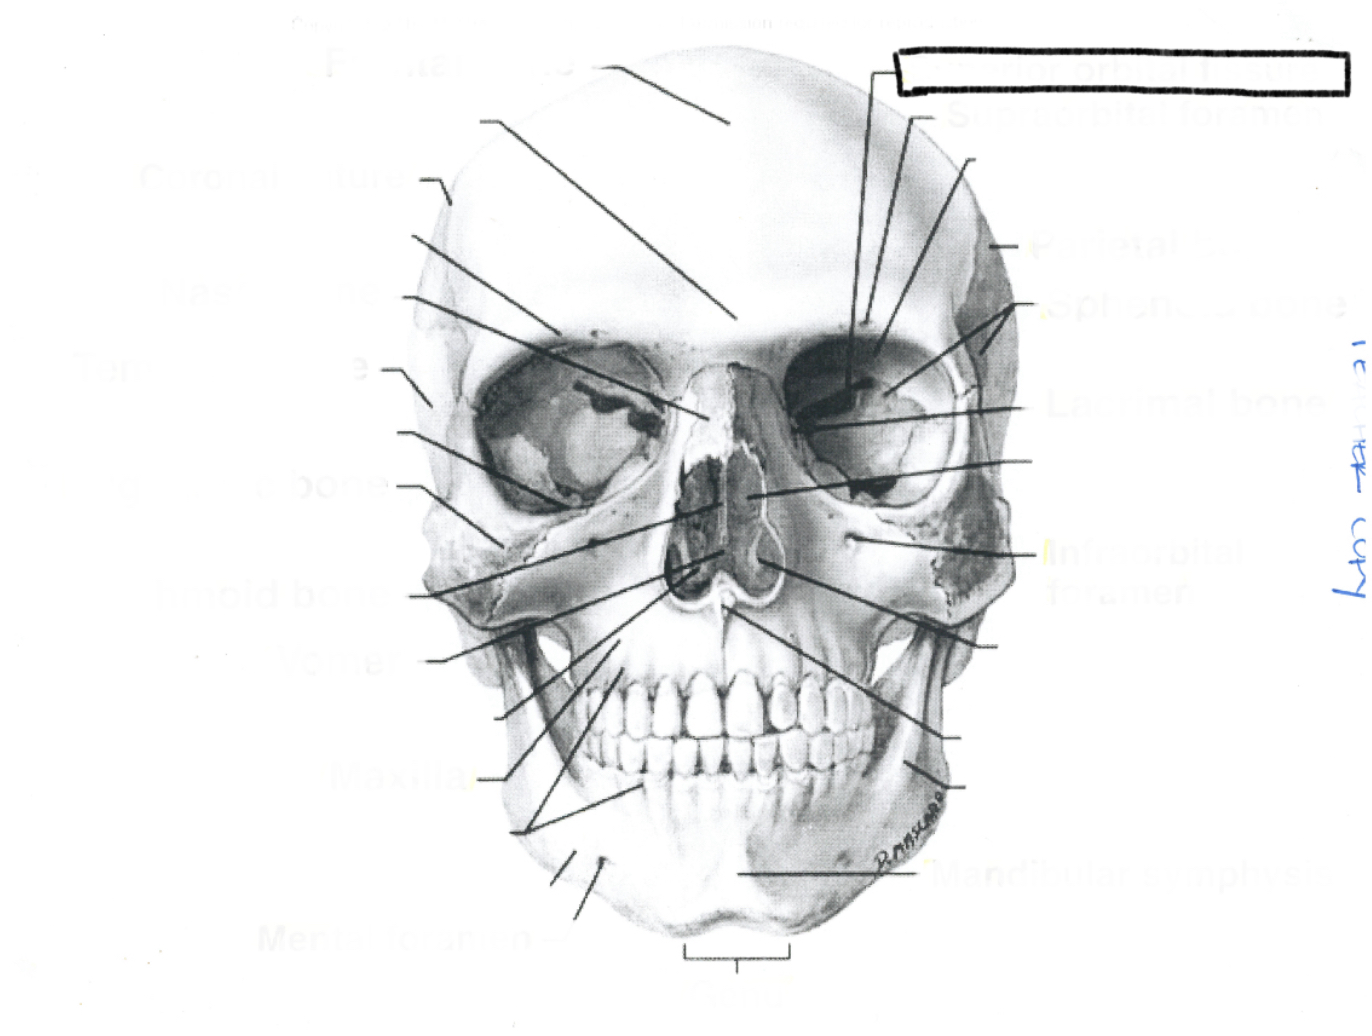

Coronal suture

Frontal bone

Coronal suture

Frontal bone

Supraorbital foramen

Sphenoid

Frontonasal suture